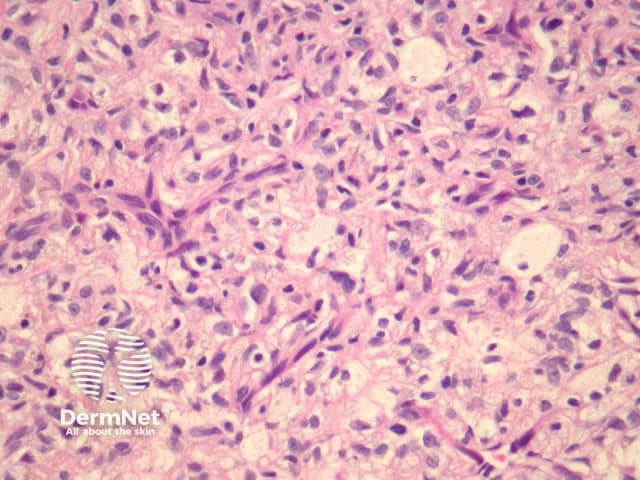

Histologically, there are cleft-like haemorrhagic spaces within the centre of the aneurysmal dermatofibroma that mimic vessels but lack an endothelial lining. The tumour itself tends to be fairly cellular (figure 7, 8). Haemosiderin deposition may be an additional feature. Aneurysmal dermatofibroma may be mistaken for a vascular tumour, however, clues to the diagnosis include surrounding features of dermatofibroma, and endothelial cell markers are positive in normal vessels only and not the aneurysmal spaces.

Figure 7

Figure 8